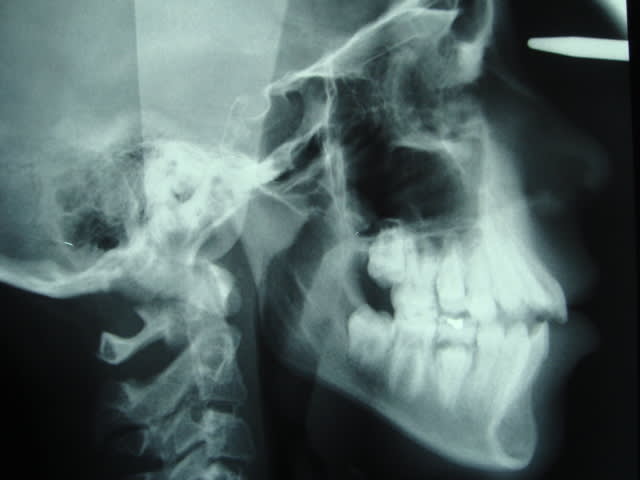

Voici la tele que j'ai recupéré, la patiente a maintenant 14,5 ans. le traitement a commencé alors qu'elle avait 13 ans mais elle n'a pas suivi ces rendez-vous régulièrement.

Pour l'instant, une feo avec traction verticale pour avoir comme effet une bascule du maxillaire vers le bas serait souhaitable d'après vos réponses. Et pourquoi pas des élastiques d'intercuspidation et mécanique de classe 2 et pendant combien de temps?

J'aime bien les elastics de cl II, bigrement efficaces, mais dans ce cas particulier, ne risquent ils pas d'accentuer l'hyperdivergence???

J'ai bien peur qu'en plus de la FEO qui vont en effet induire une rotation mandibulaire favorable , il faille mettre des elastics verticaux.

Cher vador,

Dans un cas comme celui là, la TéléRx. datant de 2 ans, je referai une nouvelle Rx. avant de prendre une décision.

Bref revenons au cas, d'apres la radio je trouve que la beance etait la avant de commencer et cela n'a pas ete pris en charge pendant la premiere partie du traitement!!! Donc il faut le faire maintenat au plus vite. La FEO a traction verticale c'etait mon idee et je la maintiens pour basculer le plan bispinal et favoriser une rotation anterieure de la mandibule ce qui corrige la classe II et reduit la beance. C'est une FEO de controle vertical du plan occlusal et non pas une force orthopedique. Il faut prendre les 7 aussi si cela n'a pas ete fait. Les elastiques de classe II dans une typologie aussi defavorable risque d'aggraver la tendance verticale et ce qu'on peut gagner sagittalement on le perd verticalement. A mon avis cela peut etre necessaire a la fin pour parfaire la classe I.